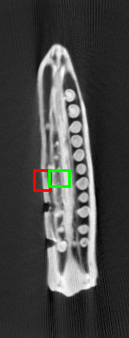

Figure 3: Radio-frequency ablation dataset. (a) through (g): one of the slices (512 x 512) from each of the 8 scan volumes of a longitudinal study dataset of the liver. Note that in volumes (a) through (g), the needle (shown in red in (f)) approaches the target tumor. (h) the organ after the ablation: this slice is displayed on a separate intensity scale to enable proper viewing of the region marked in green that shows the after-effects of ablating the tumor.

The dataset from this longitudinal medical study consists of 8 scans taken during the ablation procedure. We demonstrate our method for 2D reconstruction by choosing a single slice from each of the 8 volumes as our dataset. Note that all these 8 slices are located at the same index 222The notion of same index (slice number corresponding to the same depth) makes sense in the context, because in such problems, the different scans are aligned with each other. within each of the respective volumes. Fig. 3 shows the chosen set of 2D slices (each of size 512×512512512512\times 512) from the different volumes. Observe that the needle is seen in all of the first 7 slices and the effect of ablation is seen in the 8th slice.

Tracking the needle: We first choose slices 1-6 as our templates, and reconstruct slice 7 with the specific goal of tracking the needle and simultaneously reduce artefacts. Fig. 4 shows the reconstruction of slice 7 from its measurements from only 90 views. The reconstructions are quantitatively compared using SSIM.

Observing details of the ablation: Next, we choose slices 1-7 as our templates and reconstruct slice 8 from 120 views i.e., a somewhat higher number of views this time. Fig. 5 shows the reconstructions of slice 8 by different methods. We see that the weighted prior reconstruction brings in the advantage of the prior without it adversely affecting the new regions.